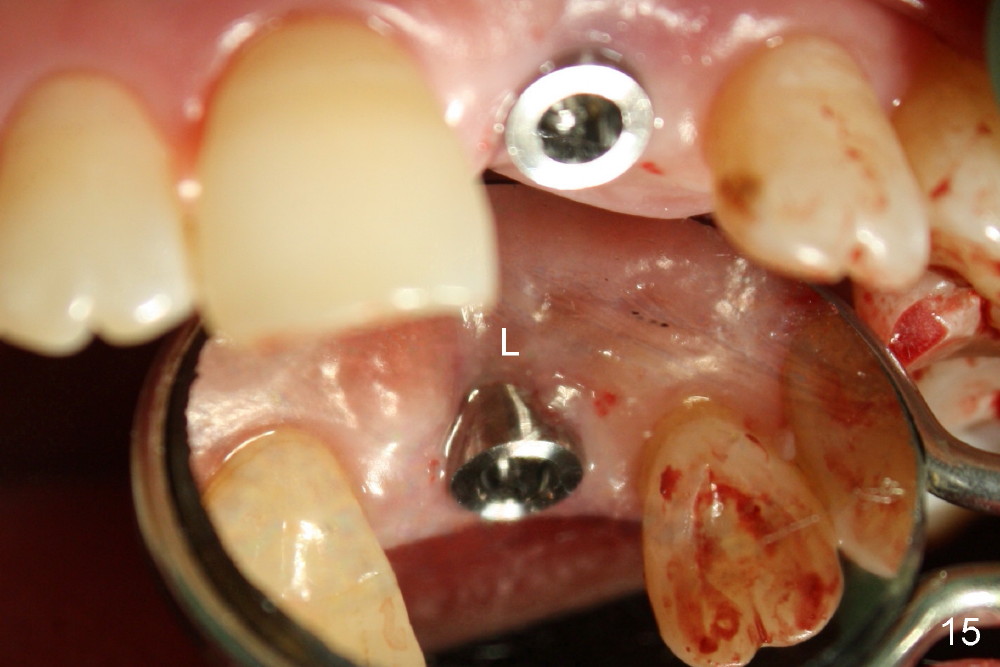

A 60-year-old lady had an abscess mesial to #9 six years ago (Fig.1,2 <), treated as a perio lesion by laser (Fig.3) and osseous surgery without bone graft (Fig.6, followed by CT exam revealing semi-circumferential bone loss (Fig.4,5). When the perio treatment failed, attention was paid to endo aspect (Fig.7-9). In fact the pulp was found to be vital when access to root canal therapy was made. As expected, the treatment failed again. The palatal fistula persisted. The infection was suspected to be a source of remote immediate implant site (#30). The tooth #9 was extracted. It appears that there is a semilunar crack line in the linguomesial root (Fig.12). When the socket healed 2 weeks post extraction (Fig.10), the #30 buccal defect was debrided with bone graft. There was no bone resorption 4 weeks post extraction (Fig.11); a 4.5x17 mm implant was placed (Fig.13-15). An immediate provisional was fabricated (Fig.16-18). Fig.19,20 were taken 3 months post implantation and 7 months post cementation, respectively. Dense bone forms around the implant coronally 4 years 5 months post cementation (Fig.21), while the gingiva is healthy palatally (Fig.22) and buccally (Fig.23).